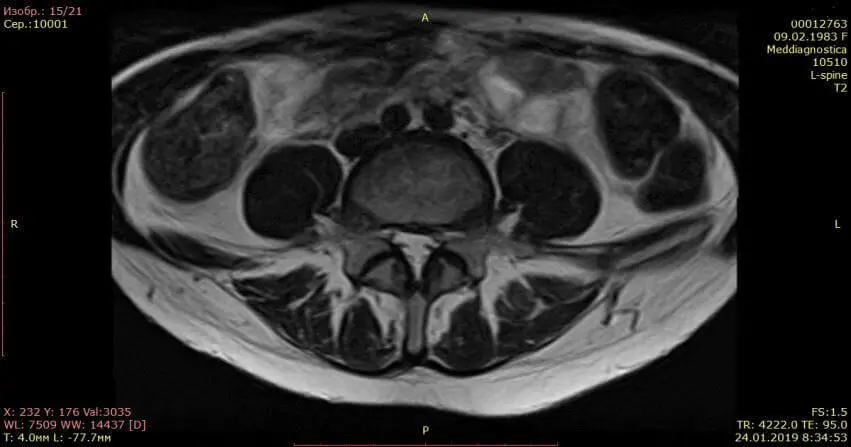

Контрольный МРТ, через 5 месяцев показал полное отсутствие грыжи диска (см. снимки Ирины ниже):

Обратите внимание на даты проведения МРТ в правом нижнем углу. МРТ исследования проведены на одном аппарате 1.5 теслы в клинике «Меддиагностика» в процессе лечения Ирины. МРТ позвоночника позволяет отследить динамику уменьшения грыжи диска.

Спасибо центру «Меддиагностика» за оказанную помощь. Боли в спине меня беспокоили уже давно, однако я особо не придавала этому значения, обходилась то мазями, то массажами, которые приносили облегчение лишь на время. Забила тревогу я только тогда, когда боли начали отдавать в ногу и пошло онемение ноги.Я сразу сделала МРТ, на котором обнаружилась межпозвоночная грыжа 12 мм, которая сдавливала седалищный нерв. Пропила таблетки противовоспалительные, витамины, но облегчения особого не было, боль в спине уменьшилась, но нога продолжала неметь.Ходили на консультацию к нейрохирургу, но там ответ один — оперативное лечение. Операцию я делать побоялась, решила испробовать другие методы. Друзья мне посоветовали обратиться в центр «Меддиагностика». Мне здесь назначили курс лечения позвоночника и сказали, что с операцией спешить не стоит, прооперировать всегда можно успеть. Я прошла сухую вытяжку позвоночника, курс массажей, уколы вдоль позвоночника. Ногу стало постепенно отпускать и на 6-7 сеанс прошло онемение пальцев.После лечения назначили лечебную физкультуру для закрепления эффекта. В итоге моя грыжа с 12 мм уменьшилась до 2мм! Я очень рада, что попала в этот центр, где работают профессионалы своего дела, которые ставят людей на ноги и оказывают реальную помощь. Отдельно большое спасибо профессору Гонгальскому Владимиру Владимировичу. Это человек с большой буквы и профессионал своего дела!!! Рекомендую всем этот центр. Спасибо Вам большое, что Вы есть! С уважением, Ремига Ирина